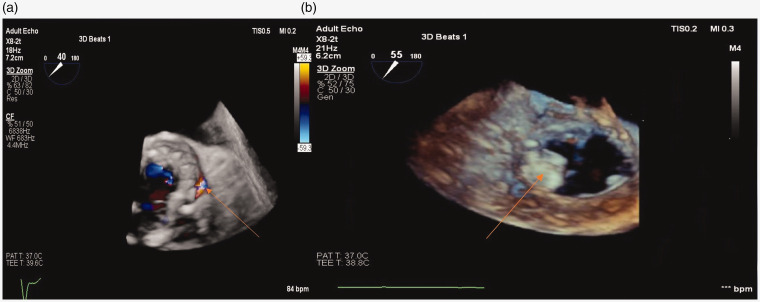

经导管技术越来越多地用于瓣旁泄漏闭合。我们报告使用“融合技术”(EchoNaviagator, Phillips, Tustin, CA),将实时二维和三维经食管超声心动图与透视成像相结合,以促进瓣旁泄漏闭合。这有助于确定瓣旁泄漏的确切位置、大小、深度和形状,以便正确定位封堵器装置,从而节省时间和精力。

Transcatheter technology has been increasingly used for paravalvular leak closure. We report the use of "Fusion Technology" (EchoNaviagator, Phillips, Tustin, CA) that combines real-time 2 and 3 dimensional trans-esophageal echocardiography with fluoroscopy imaging to facilitate paravalvular leak closure. This could help to identify the exact site, size, depth and shape of the paravalvular leak for proper positioning of the occluder device, which may result in saving time and effort.